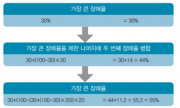

| 2019년 5월 28일 (화) 01:34 | 비뇨기계장애감정지침서 그림1.png (파일) |  |

92 KB | Sjlee | 1 | |